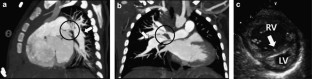

We report a very rare case of isolated multiple pulmonary arterial calcification with severe bilateral peripheral pulmonary arterial stenosis diagnosed in utero. Despite treatment with bisphosphonate for 6 months, systolic right ventricular pressure increased persistently and surpassed left ventricular pressure. After successful bilateral pulmonary arterioplasty at 13 months of age, the patient showed decreased systolic right ventricular pressure with normal interventricular septal configuration. This is the first case report for an isolated pulmonary artery calcification without other arterial calcification proven by non-contrast computed tomography of a living patient.